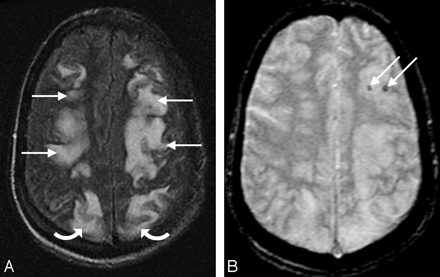

A 50-year-old woman with fever and severe hypertension. A and B, FLAIR MR image demonstrates sulcal signal abnormality and PRES vasogenic edema in the left frontal lobe (arrowheads) and edema in the occipital lobes bilaterally (open arrows). C, Gradient MR image demonstrates linear low signal intensity consistent with sulcal subarachnoid hemorrhage (arrows). D, CT image demonstrates high attenuation consistent with the MR imaging appearance, further confirming the sulcal subarachnoid hemorrhage (arrow).